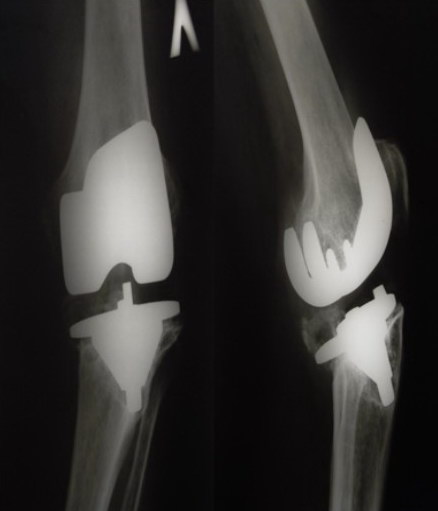

Приклад 2. Хвора  М. 68 років. Діагноз: лівобічний деформівний IVст. гонартроз, стан після ТЕП лівого КС (2014р.). Під час виконання оперативного втручання компоненти ендопротезу встановлені в варусному положенні. Асептична нестабільність компонентів ендопротеза, тотальна  нестабільність зв’язкового апарату компонентів колінного суглоба (2017 р.)  Хворій виконано ревізійне ендопротезування: видалення компонентів ендопротезу, виявлений дефект виростку великогомілкової кістки тип Т2А за класифікацією АОRI [G.A. Engh, C.H. Rorabeck, 1997]. Враховуючи стан зв’язкового апарату використаний зв’язаний ендопротез типу Hinch.